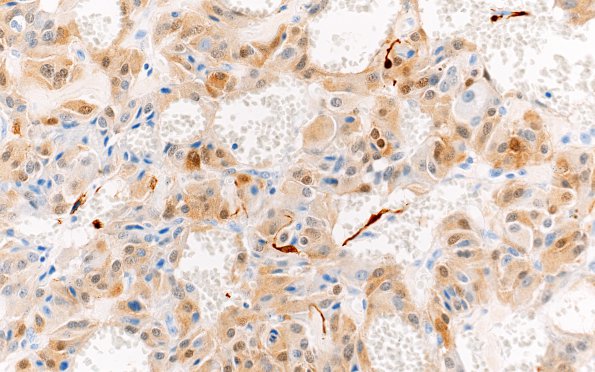

Washington University Experience | NEOPLASMS (NEURONAL) | Paraganglioma - Cauda Equina Neuroendocrine Tumor | 3D3 Paraganglioma (Case 3) 1 S100 40X

Immunoreactivity for S100 protein stains a subset of the chief cells, as well as some smaller tumor cells with slender processes consistent with sustentacular cells. (SYN IHC)